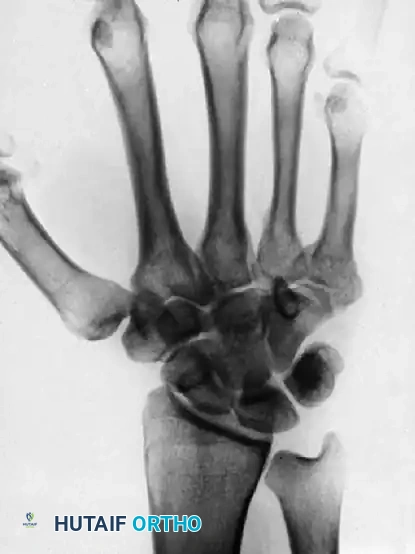

FIGURE 67-30 B-D: Posteroanterior, Lateral, and Oblique radiographic views demonstrating the dorsal dislocation of the fourth and fifth carpometacarpal joints.

Standard posteroanterior (PA), lateral, and oblique radiographs are mandatory. However, the overlapping anatomy of the carpus can obscure subtle subluxations.

> CLINICAL PEARL: Always obtain a true lateral radiograph of the hand. The metacarpal shafts should align perfectly parallel. Any dorsal divergence of the 4th or 5th metacarpal shafts relative to the 3rd metacarpal is highly indicative of a CMC dislocation. If plain films are equivocal, a CT scan is the gold standard for evaluating articular comminution and subluxation.